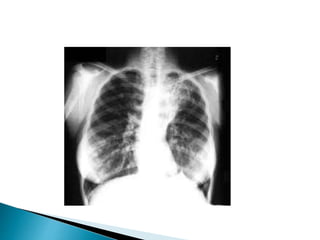

Diagnosis TB aktif :

a. hasil radiologi (biasanya melalui sinar-X

dada)